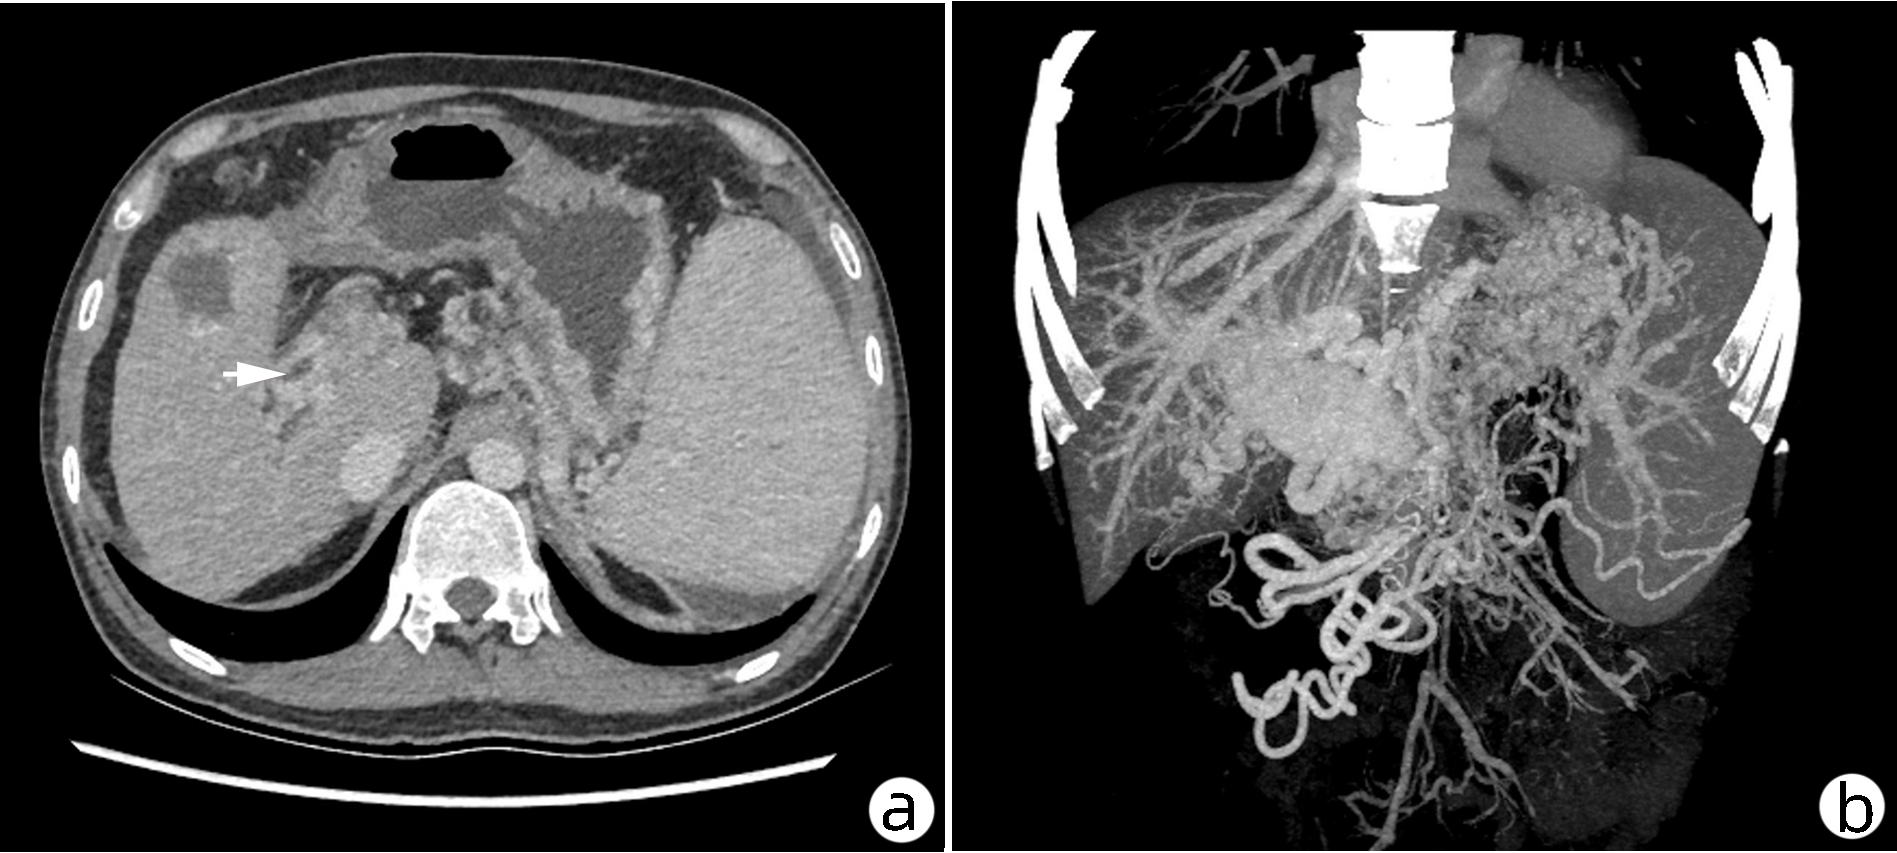

肝窦阻塞综合征成功诊治1例报告

耿雯倩, 朱浩, 杨鑫, 李婉玉, 许芳, 蔡艳俊, 高普均

2023, 39(2): 397-400. DOI: 10.3969/j.issn.1001-5256.2023.02.023

摘要(1461) HTML (477) PDF (2418KB)(136)

摘要: